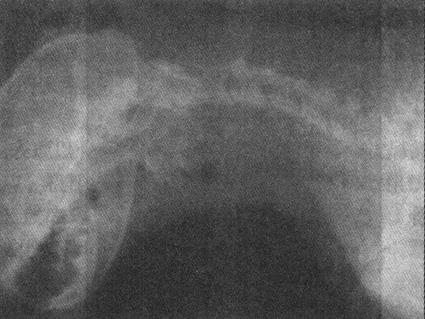

4.胸腔积液 X线检查仅可证实胸腔积液,但不能区别液体性质。胸腔积液包括游离性、包囊性和叶间积液。极少量的游离性胸腔积液(小型犬、猫<50ml;中、大型犬<100ml),在X线上不易发现。游离性胸腔积液量较多时,站立侧位水平投照显示胸腔下部均匀致密的阴影,其上缘呈凹面弧线(图1-12)。大量游离性胸腔积液时,心脏、大血管和中下部的膈影均不可显示。当液体被纤维结缔组织包围并因粘连而固定某一部位,形成包囊性胸腔积液时,X线表现为圆形、半圆形、梭形、三角形,密度均匀的密影。如发生于肺叶之间的叶间积液,X线显示梭形、卵圆形、密度均匀的密影。

图1-12 犬胸腔积液

侧位显示胸腔下部均匀致密的阴影,上缘呈3个凹面弧线,心脏和心胸三角区不可显示